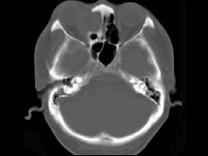

女,38岁,右侧眼球运动障碍伴眼球突出4个多月,CT扫描如图,正确的描述或诊断是()

A.右侧筛窦内可见囊性肿块影,边缘光整

B.囊性肿块向右侧眼眶内突入,压迫内直肌

C.右侧眶内壁呈受压变薄、断裂

D.右侧筛窦黏液囊肿

E.筛窦癌

[多选题] 女,38岁,右侧眼球运动障碍伴眼球突出4个多月,CT扫描如图,正确的描述或诊断是()A .右侧筛窦内可见囊性肿块影,边缘光整B .囊性肿块向右侧眼眶内突入,压迫内直肌C .右侧眶内壁呈受压变薄、断裂D .右侧筛窦黏液囊肿E .筛窦癌

[多选题] 女性38岁,右侧眼球运动障碍伴眼球突出4个多月,CT扫描如图,请选择正确的描述和答案()A . 右侧筛窦内可见囊性肿块影,边缘光整B . 囊性肿块向右侧眼眶内突入,压迫内直肌C . 右侧眶内壁呈受压变薄、断裂D . 考虑为右侧筛窦黏液囊肿E . 考虑为筛窦癌